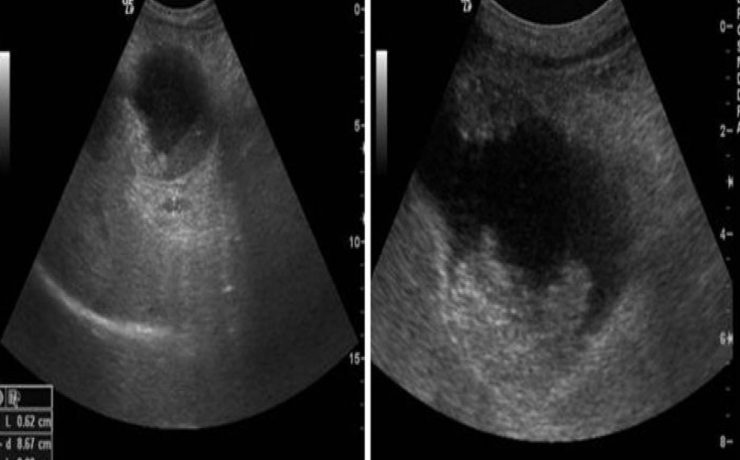

Hiperplasia prostática benigna

La hiperplasia prostática benigna (HPB) es muy prevalente en atención primaria; es el principal motivo de consulta por problemas urológicos en el hombre y es el primer diagnóstico que debemos pensar ante un paciente mayor de 50 años que consulta por síntomas obstructivos y/o irritativos. El diagnóstico de HPB es